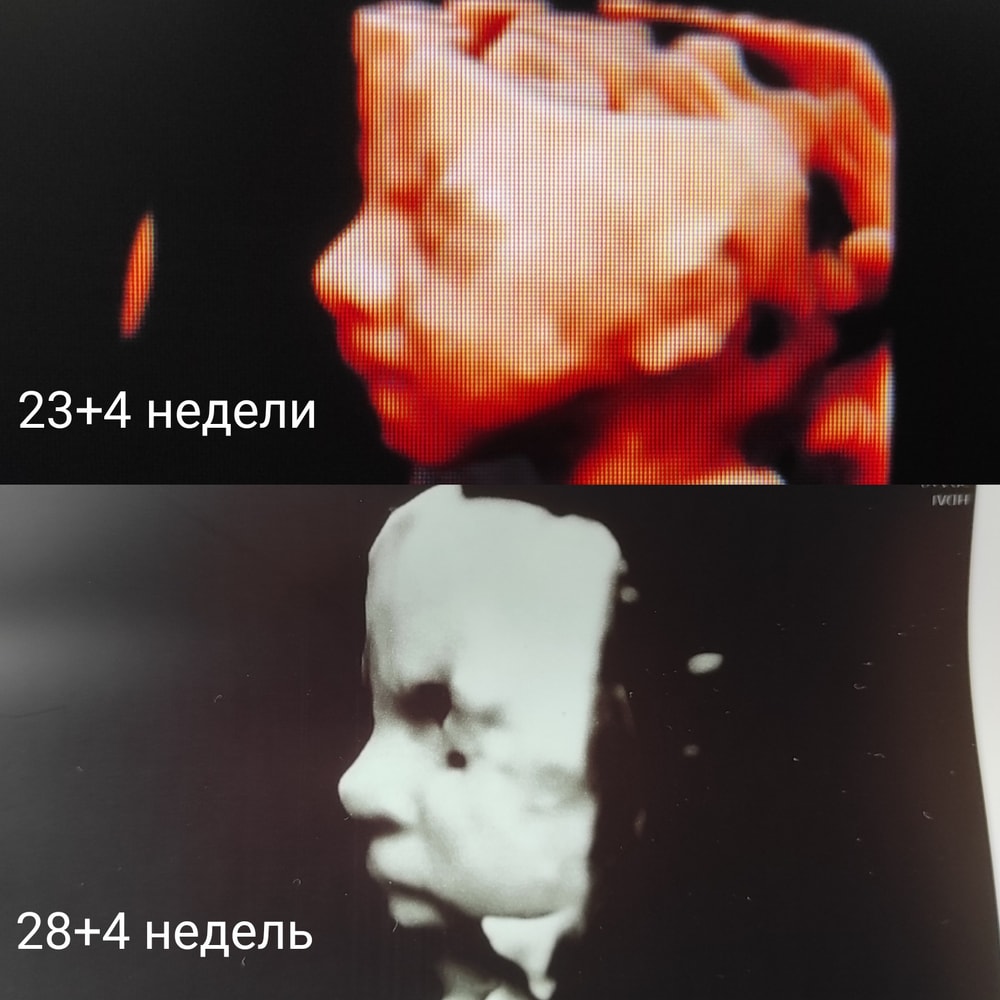

Первый раз ходила на 24 неделе, малышка очень мило палец сосала и улыбалась))) второй раз на 29, лежала спиной, не хотела поворачиваться, когда повернулась, моську ручками закрывала, но фото сделать удалось

Вот здесь 21+5. А вот здесь 22+6 (здесь были фото). Это на разных аппаратах, в разных больницах, у разных врачей.

В целом, малыш похож, но вот в 29 недель уже копия того, каким родился. С 22 недель еще менялся, конечно.